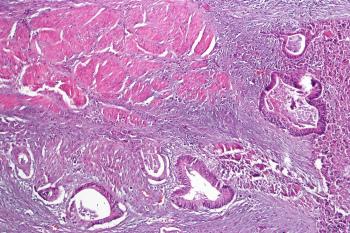

Аденокарцинома кишечника

Этот гистологический тип новообразований встречается чаще всего – в 80% случаев. В зависимости от степени дифференцировки аденокарциномы бывают:

- высокодифференцированными – в структуру опухоли входят развитые клетки, которые имеют много схожих признаков с неопухолевыми эпителиальными клетками кишечника;

- низкодифференцированными – новообразование развивается из неразвитых клеток, характеризующихся агрессивным ростом;

- умеренно-дифференцированными – опухоль, в состав которой входят высоко- и низкодифференцированные клетки.